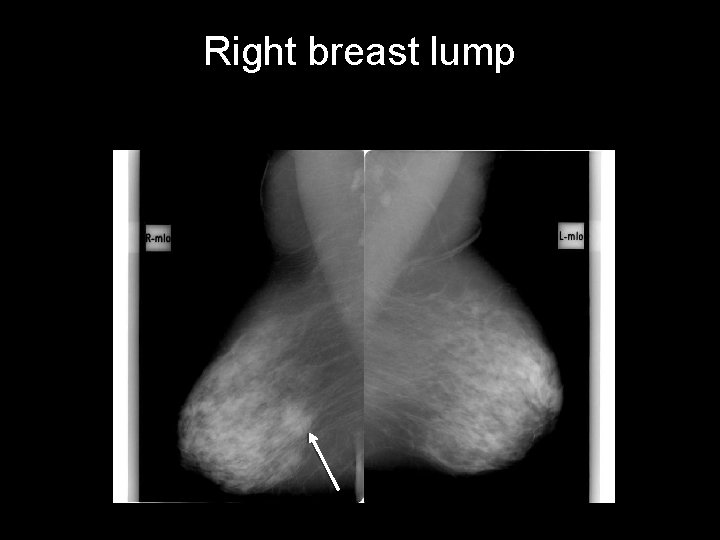

Right breast lump CASE 2 • • Right breast lump Age: 71 years old Gender: Female Race: Middle eastern • First study? – Ultrasound – Mammography – MRI w contrast

Right breast lump lymph nodes • speculated opacity at the middle of the lower part • focus of macrocalcification adjacent to the mass • Bilateral axillary lymph nodes microcalcifications mass

Right breast lump • • irregular mass, hypoechoic, with heavy post acoustic shadowing and hypervascularity the lymph nodes appear reactionary with preserved sinus BREAST CANCER (BIRADS V) http: //radiopaedia. org/cases/breast-cancer-7